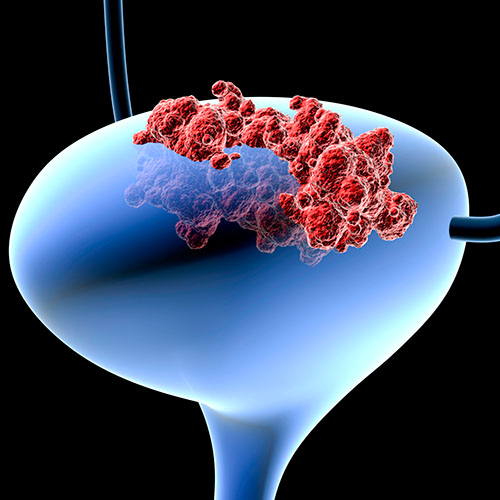

A bladder is the hollow organ in that pelvis that stores urine before it leaves the body. Urine is made by the kidneys and then carries to the bladder through ureters (tubes), and when you urinate the muscles in bladder contracts and urine is forced out of the bladder through the urethra. Bladder cancer occurs when the cells in the urinary bladder start to grow uncontrollably. As more cancer cells develop, they start forming tumours and spread to other parts of the body.

In most cases, bladder cancer starts in the innermost lining of the bladder – called the urothelium or transitional epithelium. As the cancer grows through these layers in the bladder wall, it becomes advanced, making it harder to treat. Over time the cancer can spread to other parts of the body such as distant lymph nodes, the bones, the lungs and the liver.

Bladder cancer tends to grow slowly and often does not spread to other parts of the body. When it does spread, it is called metastatic bladder cancer. If it spreads, bladder cancer may go to lymph nodes in the pelvic area or invade other nearby organs, such as the prostate or uterus. Bladder cancer can also spread to distant areas, most commonly to the lungs, bones, and liver.